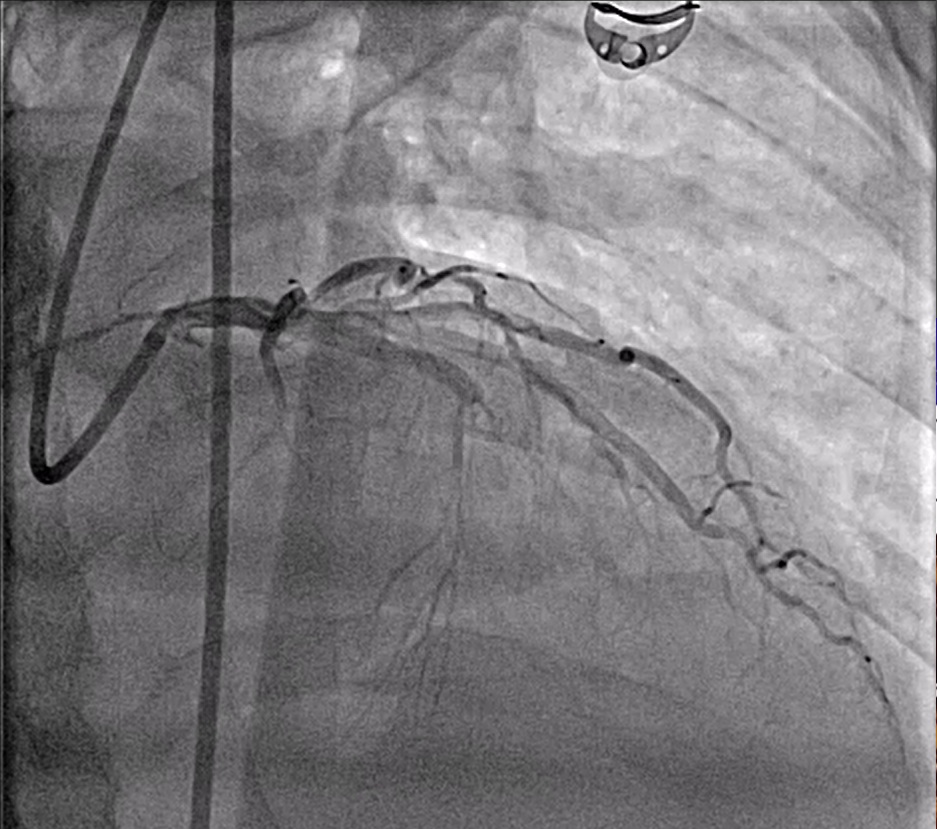

CAG was performed with Right femoral approach with Dx catheterJR 6/4 Fr, GD EBU 7/3.5 Fr showed

Right dominant

LM : normal.

LAD : total occlusion LAD stent thrombosis.

LCx : normal.

RCA : normal.

On Lucas CPR Proceed directly to PCI of LAD,

Guiding : EBU 7/3.5 to LCA

Guide wire : Turntrac to LAD

Pre dilatation : SC balloon 2.0 x 15 inflated mLAD upto 12 atm, inserted IVUS to LAD IVUS revealed neoatherosclerotic mLAD stent, SC balloon 3.0 x 15 mm inflated mLAD upto 12 atm, Rapamycin eluting stent 3.5 x 31 mm deployed mLAD upto 12 atm with POT Puff sign. Acceptable angiographic result.